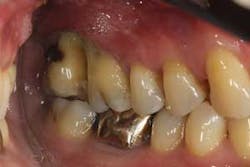

Figures 2a and 2b: Initial presentation in 2011 of the upper right and left molar area, showing advanced bone loss with furcation involvement on the molars.

At presentation, Martin was in his fifties with a medical history significant for controlled hypertension with no known food or drug allergies. He had been lackadaisical with his dental care in the past because of his busy schedule, but he was motivated to get his hygiene and treatment under control. He denied a history of smoking/alcohol/drug use. Based on his full-mouth series (figure 1) and clinical presentation, Martin had generalized, moderate bone loss with localized, severe bone loss in the posterior maxillary right and left quadrants (figures 2a and 2b) as well as the mandibular anterior incisor area (figure 3).

Martin was shocked by his diagnosis and dismayed by the hopeless prognosis he received. With a background in research as well as a questioning mind, Martin began to familiarize himself with periodontics and treatment options other than extraction and implants. He soon sought consultation with periodontal specialists to see if saving his teeth were an option. Although he was told that many of his teeth could be saved with periodontal treatment, he was again told that all of his maxillary molars needed to be extracted, including the four mandibular anterior teeth. In addition to extraction and site preservation, bilateral sinus augmentation with subsequent implant treatment would be necessary. Prosthetic restoration included multiple single-unit implant crowns, a four-unit implant bridge in the anterior, and various other cosmetic restorations. He was given a treatment plan that would cost close to six figures.